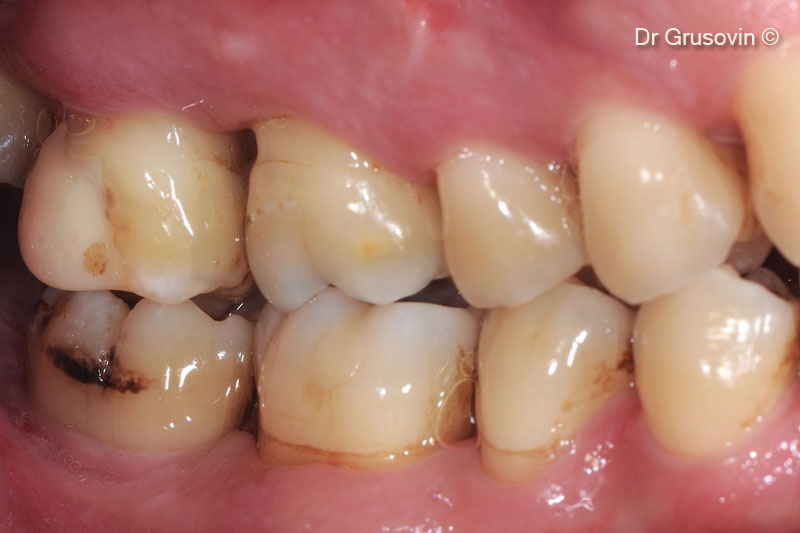

Tình hình lâm sàng sau 7 năm theo dõi.